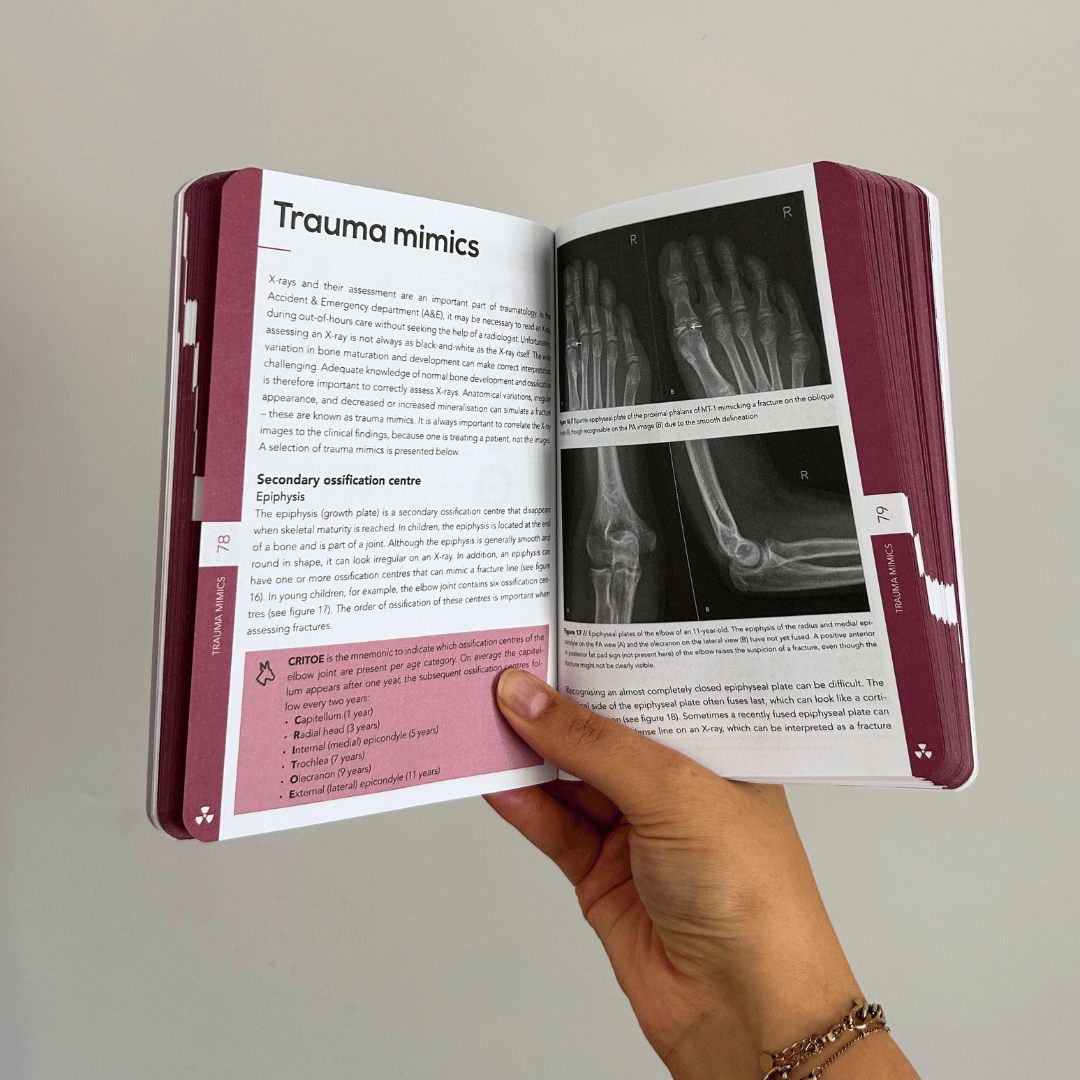

Clear, practical and visual

The Compendium Method© simplifies radiology with structured layouts, clear visuals, and diagrams – helping you understand and apply knowledge more effectively, even under pressure.